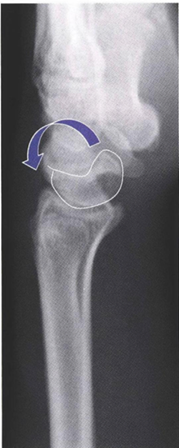

図:舟状骨シフトテスト

手関節を中間位で尺屈強制し、舟状骨結節を掌側より背側に向けて圧迫する→徐々に手関節を橈屈させて行くと、ある時急にclickを感じ、舟状骨の背側への脱臼感を感ずる)

出典:坪川直人. 関節外科 28, no. 4 (2009): 466-473.